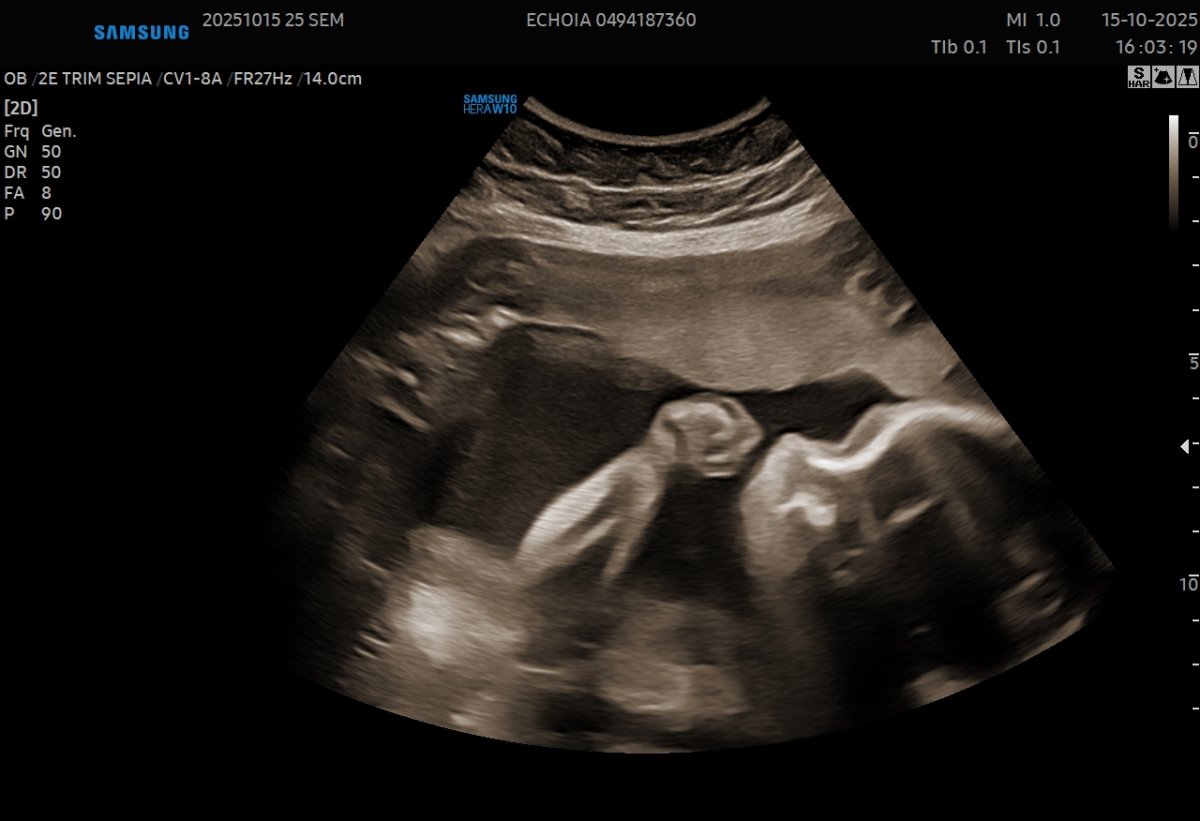

Gallerie de photos